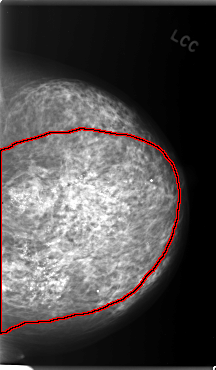

C_0071_1.LEFT_CC

LEFT_CC LINES 5912 PIXELS_PER_LINE 3456 BITS_PER_PIXEL 12 RESOLUTION 50 OVERLAY

FILE: C_0071_1.LEFT_MLO.OVERLAY

TOTAL_ABNORMALITIES 1

ABNORMALITY 1

LESION_TYPE CALCIFICATION TYPE PLEOMORPHIC DISTRIBUTION REGIONAL

ASSESSMENT 5

SUBTLETY 5

PATHOLOGY MALIGNANT

TOTAL_OUTLINES 1

BOUNDARY

FILE: C_0071_1.LEFT_CC.OVERLAY